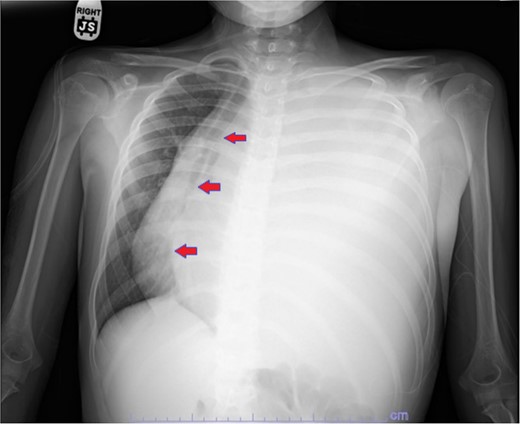

Our patient is a 10-year-old Caucasian female with a history of early adrenarche, ADHD, and COVID-19 and no past surgical history. She presented to the ED with a month-long history of persistent coughing, shortness of breath on exertion and speaking, and left-sided chest pain that began after a diagnosis of mildly symptomatic COVID-19. A physical exam revealed decreased breath sounds on the left, with a left-sided chest protrusion. A plain film and CT demonstrated a normal right lung, with a significant mediastinal shift toward the right, displacement of the heart into the right hemithorax, with complete whiteout of the left hemithorax, and demonstrating a mix of solid and cystic foci, with a round opacification at the left lung base (Figs 1 and 2). The patient underwent an uncomplicated left thoracotomy with excision of two masses, one being 22.5 × 21.0 × 10.5 cm and the other being 13.5 × 11.5 × 6.2 cm. These masses weighed 2394 g in aggregate. The specimens consisted of well-encapsulated tumors attached to the posterior aspect of the chest wall. A regional, positive lymph node measuring 3.0 × 2.2 × 1.0 cm was also resected. Due to the large size of the tumor and the requirement for clean margins, parts of the latissimus dorsi and serratus anterior muscles were also resected. By postoperative day (POD) 0, the left lung had already filled the left hemithorax, and the mediastinal shift had corrected (Fig. 3). The chest tube was removed on POD 5, and a plain film showed continued expansion of the lung to full size and resolving pulmonary edema and atelectasis (Fig. 4). The patient was discharged home on POD 5. The tumor staging was T4N1M0. The tumor was positive for vimentin, CD56, synaptophysin, chromogranin, and NSE. The tumor was negative for pancytokeratin, Cam5.2, EMA, S100, desmin, SMA, SOX10, HMB45, CD117, DOG1, CD99, PR, CD68, WT1, CD30, p53, Alk1, GFAP, and nuclear β-catenin. Next-generation sequencing showed an MGA:NUTM1 fusion, supporting a final diagnosis of high-grade MGA:NUTM1 fusion SCS. Given the size and grading of the tumor, the patient underwent adjuvant CT-RT with ifosfamide, doxorubicin, and proton beam radiotherapy, with supportive doses of MESNA and dexrazoxane for 4.5 months post-operatively. The basis of this treatment is ARST0332 Arm C [6]. Before treatment initiation, the patient underwent an uncomplicated left oophorectomy for reproductive cryopreservation. A PET/CT prior to CT-RT showed hypermetabolic activity in several areas. These included the pleural resection margin, a mediastinal lymph node concerning for metastasis versus postsurgical change, and a left axillary lymph node concerning for metastatic disease. During treatment, the patient contracted human metapneumovirus and rhino/enterovirus, resulting in febrile neutropenia. The patient was successfully treated with blood and platelet transfusions and pegfilgrastim. Upon completion of CT-RT, PET/CT imaging showed no evidence of residual disease, with minimal focal hypermetabolic activity as compared to the previous imaging (Fig. 5).

Plain film on postoperative day 0 depicting the recovery of the left lung post-surgical resection.